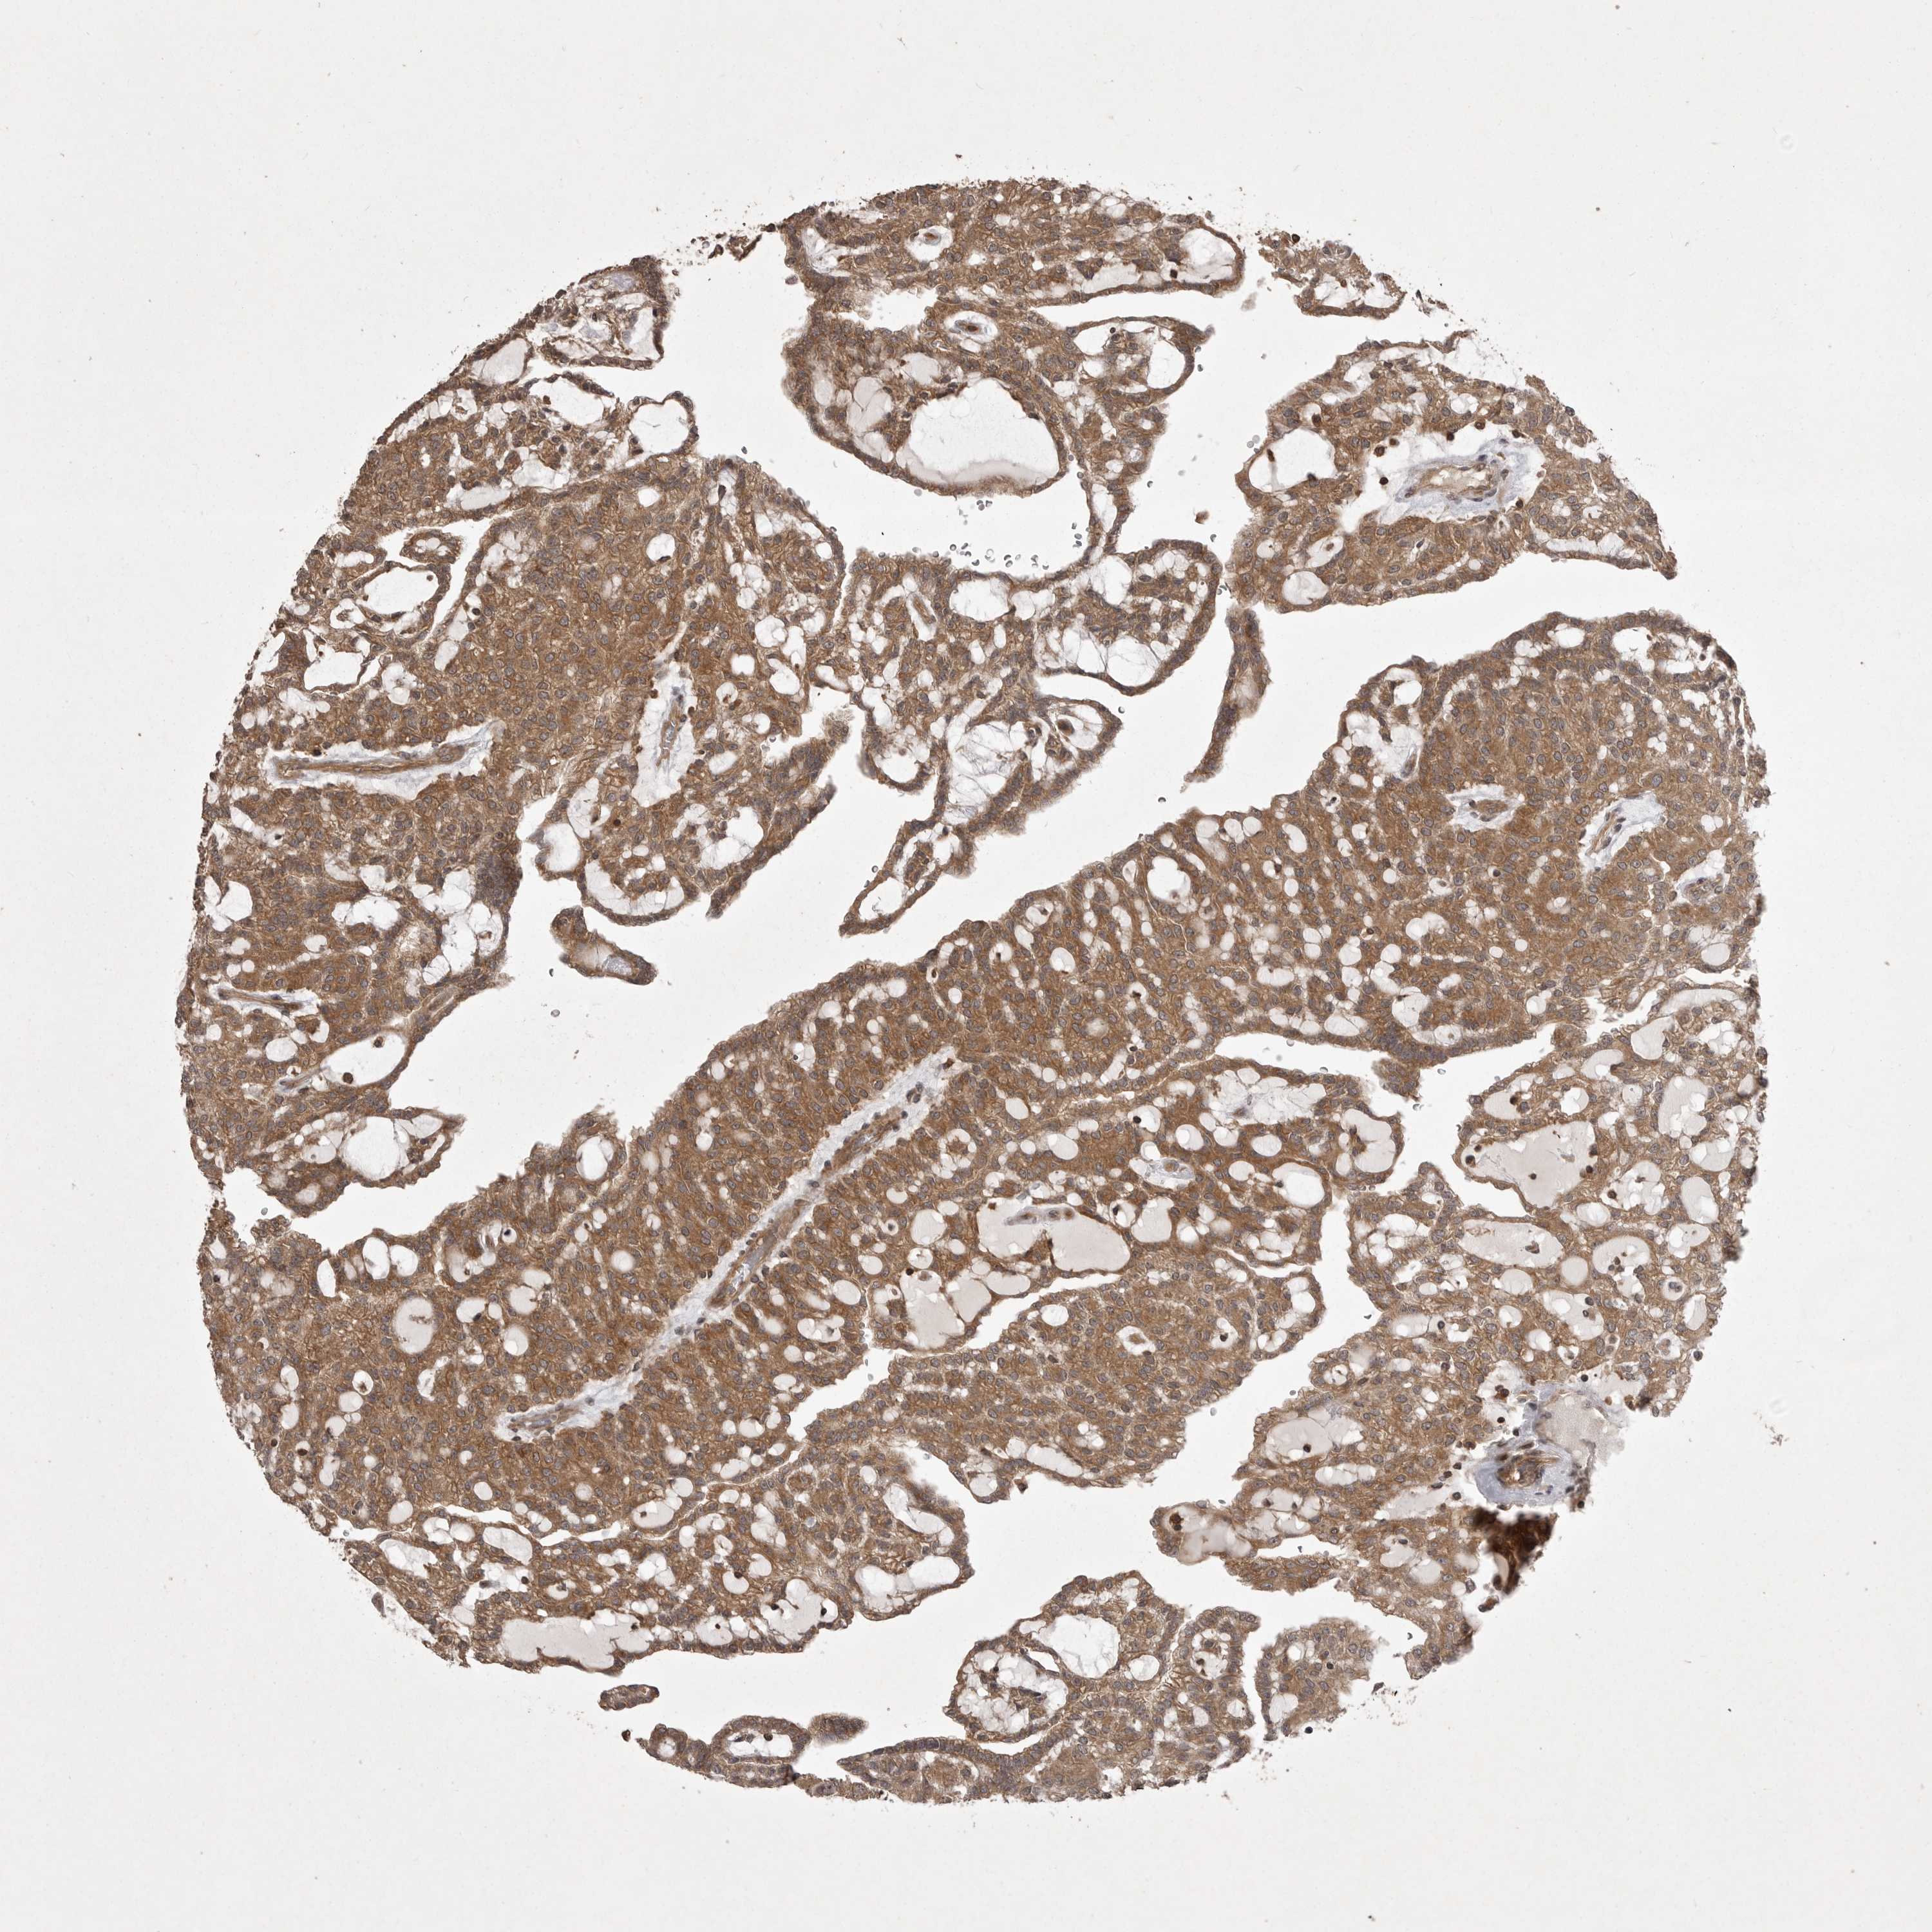

KIDNEY RENAL CLEAR CELL CARCINOMA (VALIDATION) - Interactive survival scatter ploti

The Survival Scatter plot shows the clinical status (i.e. dead or alive) for all individuals in the patient cohort, based on the same data that underlies the corresponding Kaplan-Meier plots. Patients that are alive at last time for follow-up are shown in blue and patients who have died during the study are shown in red.

The x-axis shows the expression levels (FPKM) of the investigated gene in the tumor tissue at the time of diagnosis. The y-axis shows the follow-up time after diagnosis (years). Both axes are complimented with kernel density curves demonstrating the data density over the axes. The top density plot shows the expression levels (FPKM) distribution among dead (red) and alive patients (blue). The right density plot shows the data density of the survived years of dead patients with high and low expression levels respectively, stratified using the cutoff indicated by the vertical dashed line through the Survival Scatter plot. This cutoff is automatically defined based on the FPKM cutoff that minimizes the p-score. The cutoff can be changed by dragging the vertical line or by entering a cutoff value in the square labeled "Current cut-off".

Under the Survival Scatter plot the p-score landscape (black curve; left axis) is shown together with dead median separation (red curve; right axis). Dead median separation is the difference in median mRNA expression between patients who have died with high and low expression, respectively. It is calculated as follows: median FPKM expression of dead patients with high expression - median FPKM expression of dead patients with low expression. This is intended to aid the user in visually exploring custom cutoffs and the associated p-scores and dead median separation.

Individual patient data is displayed and can be filtered by clicking on one or more of the category buttons on the top of the page. Categories describing expression level and patient information include: high, low, alive, dead, female, male and tumor stages. The scale of the x-axis can be toggled between linear and log-scale by clicking on the "x log" button. Mouse-over function shows TCGA ID, patient information and mRNA expression (FPKM) for each patient.

& Survival analysisi

Kaplan-Meier plots summarize results from analysis of correlation between mRNA expression level and patient survival. Patients were divided based on level of expression into one of the two groups "low" (under cut off) or "high" (over cut off). X-axis shows time for survival (years) and y-axis shows the probability of survival, where 1.0 corresponds to 100 percent.

STK24 is validated prognostic, high expression is favorable in Kidney Renal Clear Cell Carcinoma (validation)

Best expression cut offi

Based on the FPKM value of each gene, patients were classified into two groups and association between prognosis (survival) and gene expression (FPKM) was examined. The best expression cut-off refers the FPKM value that yields maximal difference with regard to survival between the two groups at the lowest log-rank P-value. Best expression cut-off was selected based on survival analysis .

When clicking on this number, the vertical dashed line indicating cut-off, the interactive survival plot, and the Kaplan-Meier curve will be adjusted to show results based on the best expression cut-off.

: 62.94

Average pTPM 73.0

Number of samples 100